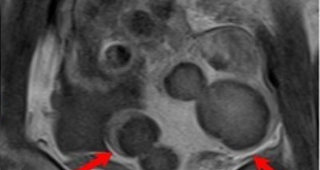

자궁근종 비수술 하이푸 치료 1년 6개월 후 임신사례입니다.자궁근종 하이푸 치료는 자궁근종 부위만 선택적으로 치료하는 시술로 자궁근종 전체적으로 시술하였습니다... 4cm 3cm 등등 다발성 자궁근종 하이푸 치료시...